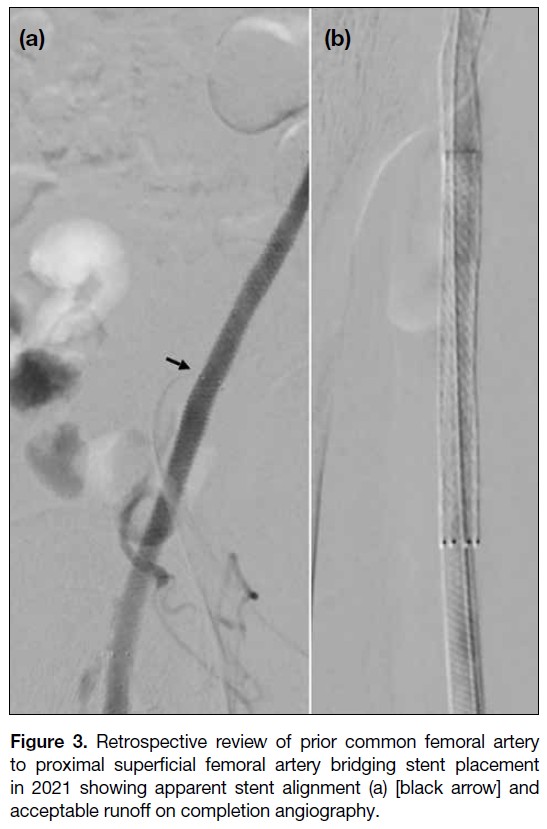

Digital subtraction angiography images in the

anteroposterior projection from the previous procedure

in November 2021 revealed apparent alignment of

the CFA-pSFA and mSFA stents, with improved

runoff post-stenting (Figure 3). Lateral views were unavailable. In view of the recurrent claudication and

Figure 3. Retrospective review of prior common femoral artery

to proximal superficial femoral artery bridging stent placement

in 2021 showing apparent stent alignment (a) [black arrow] and

acceptable runoff on completion angiography.